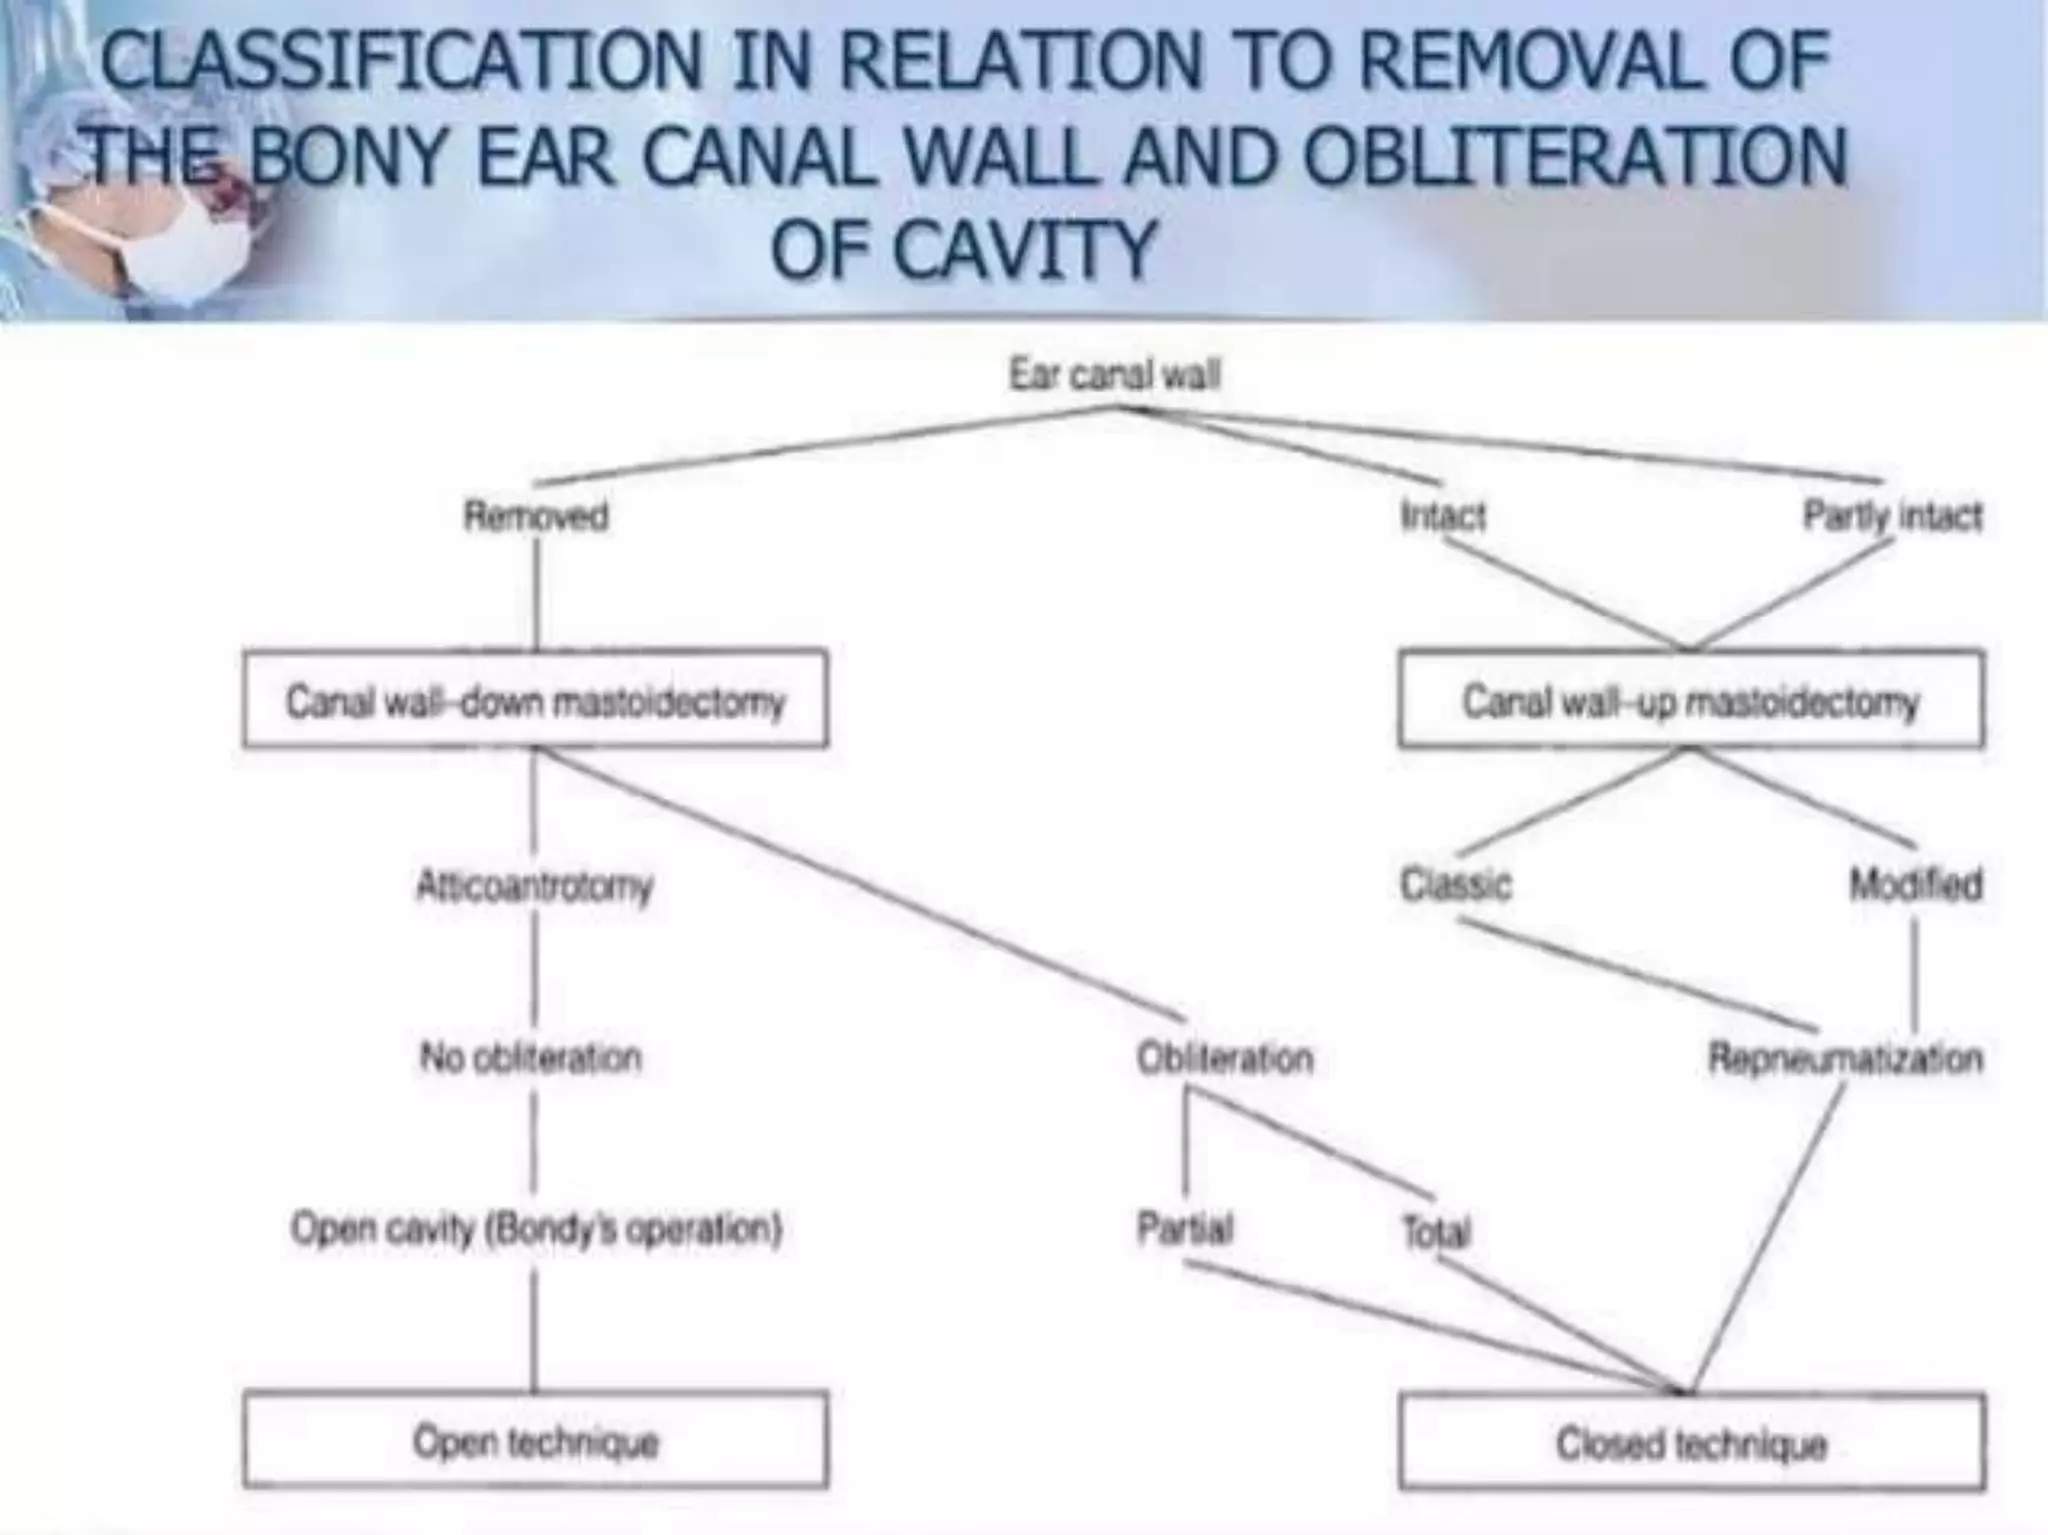

Chronic otitis media is a chronic inflammation of the middle ear and mastoid cavity that presents with recurrent ear discharge through a perforated eardrum. It has several subtypes depending on the state of the eardrum perforation and epithelium. It can be caused by prior acute otitis media, genetics, environment, eustachian tube issues, gastroesophageal reflux disease, craniofacial abnormalities, or immune deficiency.